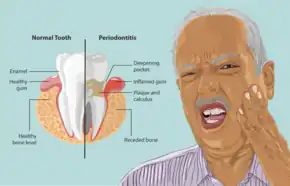

Periodontal disease, also known as gum disease, is a set of inflammatory conditions affecting the tissues surrounding the teeth.[5] In its early stage, called gingivitis, the gums become swollen and red and may bleed.[5] It is considered the main cause of tooth loss for adults worldwide.[7][8] In its more serious form, called periodontitis, the gums can pull away from the tooth, bone can be lost, and the teeth may loosen or fall out.[5] Bad breath may also occur.[1]

In some people, gingivitis progresses to periodontitis – with the destruction of the gingival fibers, the gum tissues separate from the tooth and deepened sulcus, called a periodontal pocket. Subgingival microorganisms (those that exist under the gum line) colonize the periodontal pockets and cause further inflammation in the gum tissues and progressive bone loss. Examples of secondary causes are those things that, by definition, cause microbic plaque accumulation, such as restoration overhangs and root proximity.